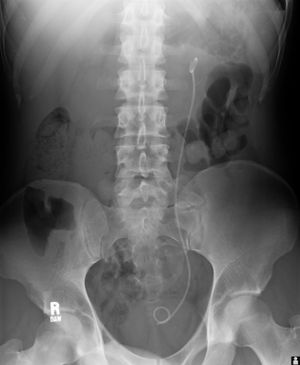

دعامات الحالب، وتستخدم لضمان عدم انسداد الحالب، الأمر الذي قد يحدث، على سبيل المثال، بسبب حصوات الكلى.

مثال لدعامات الحالب.